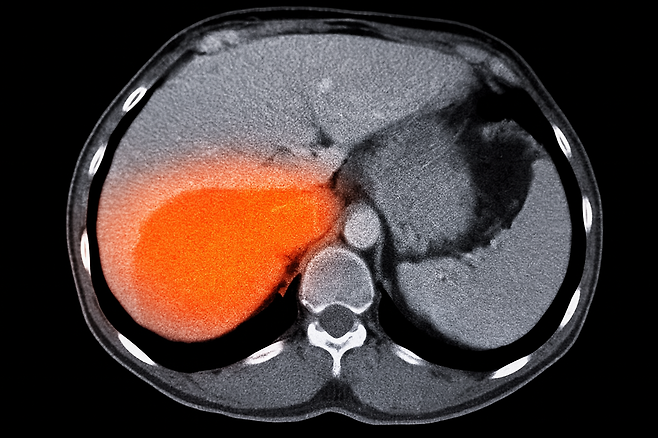

하지만 이런 증상이 반복된다면 위 건강에 적신호가 켜졌을 수 있습니다. 특히 위암은 초기 증상이 뚜렷하지 않아 조기 발견이 어렵습니다.

오늘은 위암이 시작될 때 나타날 수 있는 대표적인 증상 5가지를 알아보겠습니다.

위암은 초기 발견이 어렵지만, 작은 신호를 놓치지 않는 것이 가장 중요합니다. 위와 같은 증상이 반복된다면 바로 병원을 찾아 정확한 검사를 받으시길 권장합니다.